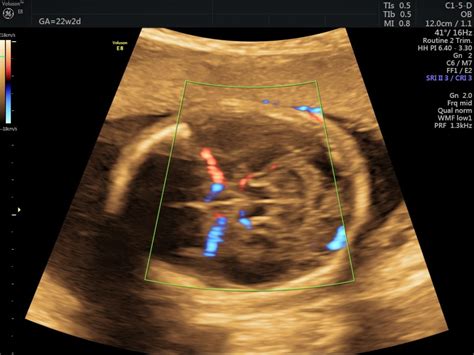

În cadrul morfologiei de trimestrul 2, se efectuează examinarea în Doppler, masurându-se astfel fluxul din ductul venos fetal, precum și fluxurile sangvine prezente la nivelul arterei umbilicale și a arterelor uterine materne.

- Inima, cele doua camere superioare (atrii) si doua inferioare (ventricule), care ar trebui sa fie egale in diametru. Valvele ar trebui sa se deschida/inchida cu fiecare bataie a inimii.

- Placenta va fi descrisa ca fiind joasa, daca se afla in apropiere sau chiar acopera orificiul intern al colului uterin. Daca placenta este praevia, este nevoie de o alta ecografie in trimestrul III pentru a-i verifica pozitia.

- Cordonul ombilical - operatorul are posibilitatea sa verifice cele 3 vase (doua artere si o vena) pentru a vedea daca lichidul amniotic este in cantitate normala.